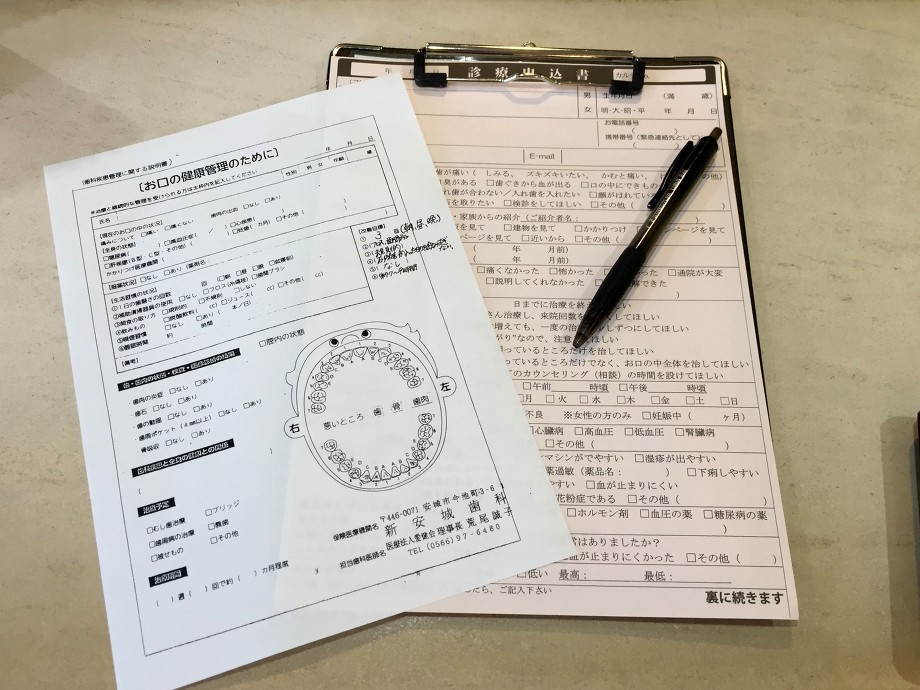

新安城歯科

新安城歯科